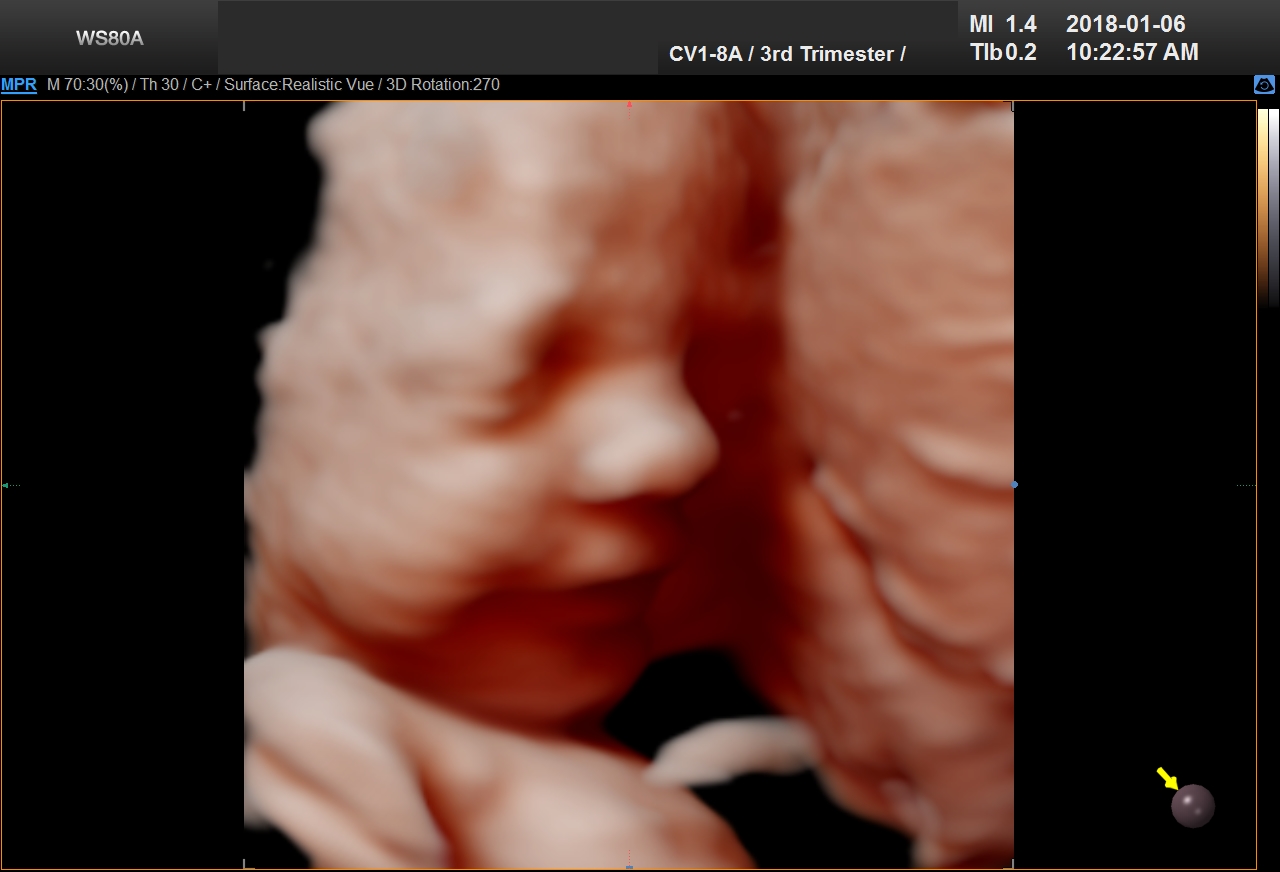

4D Ultrasound uses 3D technology in motion, with the fourth dimension being time. This technology creates videos of the baby. Parents can watch baby’s kicks, facial expressions, yawns, and even blinking eyes with 4D scans.

5D Ultrasound is the newest development in pregnancy imaging and it is patented by Samsung. It captures and combines high definition volume data to create automated images with amazing color and clarity. The bond between a new baby and the family gets even stronger when the family can view realistic pictures of baby in a 5D ultrasound.

UC Baby Calgary is the first facility which brought cutting edge 5D technology to Canada. This cutting edge new ultrasound machine provides realistic pictures of the baby using the most advanced features of ultrasound imaging. We are offering high-definition 5D ultrasound technology to create unforgettable memories without extra cost. This new ultrasound technology allows families to bond stronger to the baby, with clear views of baby’s face and movements. With 5D technology, it is even possible to notice the dimples when baby smiles!